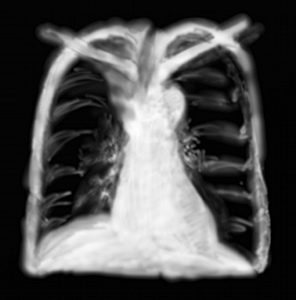

RP atélectasie lobe supérieur droit

L’atélectasie, c’est à dire l’affaissement des alvéoles pulmonaires d’un territoire par obstruction des bronchioles ou d’une bronche, peut survenir sur des poumons sains, pathologiques en dehors de toute tumeur (simple obstruction par bouchon de mucus).

Mais l’atélectasie dans le lobe supérieur est très suspecte d’une obstruction par compression extrinsèque (les sécrétions bronchiques ayant tendance à tomber par la gravité dans la bronche moyenne ou inférieure). Extrinsèque d’adénopathies tumorales ou non, ou intrinsèque par bourgeon tumoral endobronchique.